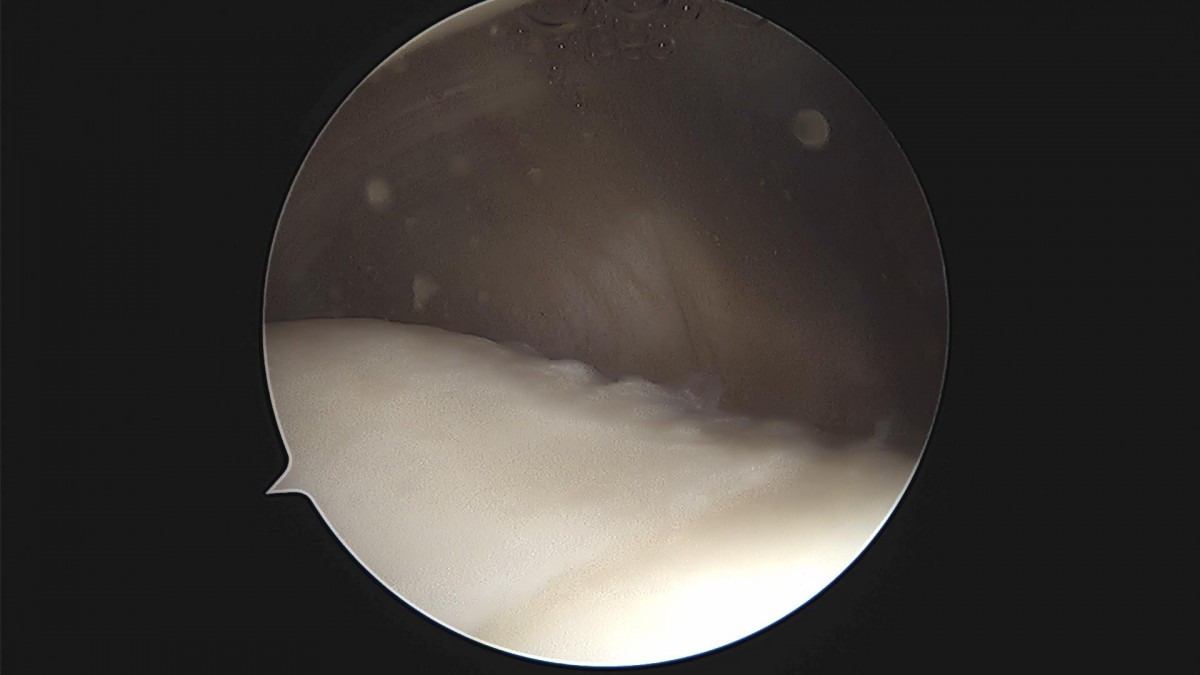

배우한 원장님 무릎 반월상 연골판 봉합술 홍재O 환자

d4279b3b94d98ed627b1644855bcf9f2_1699601484_0947.jpg